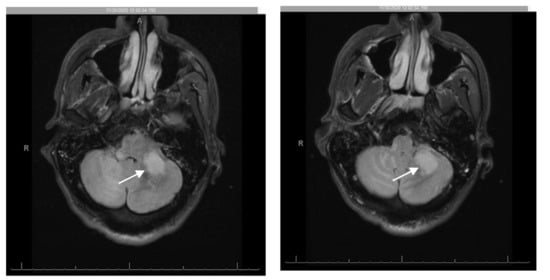

Brain magnetic resonance imaging (MRI) on admission showed increased T2 FLAIR in the brainstem and cerebellum, as well as bilateral, but asymmetrical involvement of the cerebellar peduncles, not consistent with intracranial mass or acute stroke (Figure 1). Lumbar puncture (LP) showed: white blood cells 2/μL, red blood cells 140/μL, glucose 51 mg/dL, total protein 48 mg/dL, lymphocytes 94/μL, monocytes 6/μL. The cerebrospinal fluid (CSF) polymerase chain reaction (PCR) for JC virus returned as 6400 copies/mL, suggestive of PML. Other CSF studies were unremarkable, including: Cryptococcus neoformans antigen, venereal disease research laboratory test (VDRL), Toxoplasma gondii PCR, meningoencephalitis panel, Mycobacterium tuberculosis PCR, Epstein Barr virus (EBV) PCR, cytomegalovirus (CMV) PCR, herpes simplex virus (HSV)-1 and -2 (PCR), varicella zoster virus (VZV) PCR, adenosine deaminase (ADA), angiotensin converting enzyme (ACE) and acid-fast bacilli culture and smear. Serum serological testing was positive for Toxoplasma gondii, but otherwise negative. Other negative blood tests include EBV PCR, CMV PCR, hepatitis panel, and interferon gamma release assay. CSF cytology and flow cytometry were negative for malignancy including B- or T-cell lymphoma.

Figure 1. Initial magnetic resonance imaging (MRI) brain demonstrating high T2, and high FLAIR signal in the brainstem (midbrain and pons), inferior cerebellum and bilateral (right more than left) middle cerebellar peduncles suggestive of a demyelinating process (arrow).